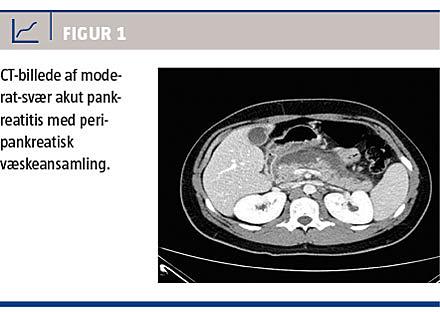

Patienten blev indlagt pga. mavesmerterne, og ved indlæggelse påvistes der normalt C-reaktivt protein-niveau på 11 mg/l og let forhøjet amylase på 77 E/l. En toksikologiscreening var negativ for alkohol (ethanol) og paracetamol. UL-skanning og CT viste ingen tegn på kolecystolitiasis, kolestase eller andet abnormt fraset akut pankreatitis. To døgn efter smertedebut blev han højfebril, og man fandt følgende niveauer: leukocytose 19,7 × 109/l, C-reaktivt protein 269 mg/l, amylase 413 E/l og laktat 2,9 mmol/l. Han blev diagnosticeret med moderat-svær akut pankreatitis i overensstemmelse med Atlantaklassifikationen [2]. Ved en CT med kontrast (Figur 1) på dag fire efter symptomdebut bekræftedes diagnosen, med komplikation i form af peripankreatisk væskeansamling.